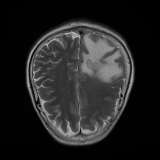

We obtain a subject-wise mean Dice score of 32.94% without any post-processing. By using a simple post-processing with erosion and dilation with filters, this number improves to 48.20% mean Dice score. In comparison, a similar study conducted by [3] consisting of a multitude of algorithms including AnoVAEGAN [4] and f-AnoGANS, obtained a best mean score of 27.8% Dice after post-processing by f-AnoGANS. Before post-processing the best method was Constrained AutoEncoder [8] with a score of 9.7% Dice. An exhaustive list is presented in Table 1. Figure 4 shows sample images of our results.

We obtain a subject-wise mean Dice score of 63.67% for the brain tumor segmentation. Utilizing a simple post-processing scheme of erosion and dilation with filter, we improve our mean Dice score to 68.01%. Figure 4 shows samples generated by our ASC-Net and Table 2 shows our before and after post-processing results. We attempted to apply f-AnoGANs [34] by following their online instructions and failed to generate good reconstructions as shown in Figure 5. The failure of AnoGANs in the reconstruction brings to light the issue with the regeneration based methods and the complexity and stability of GAN-based image reconstruction.